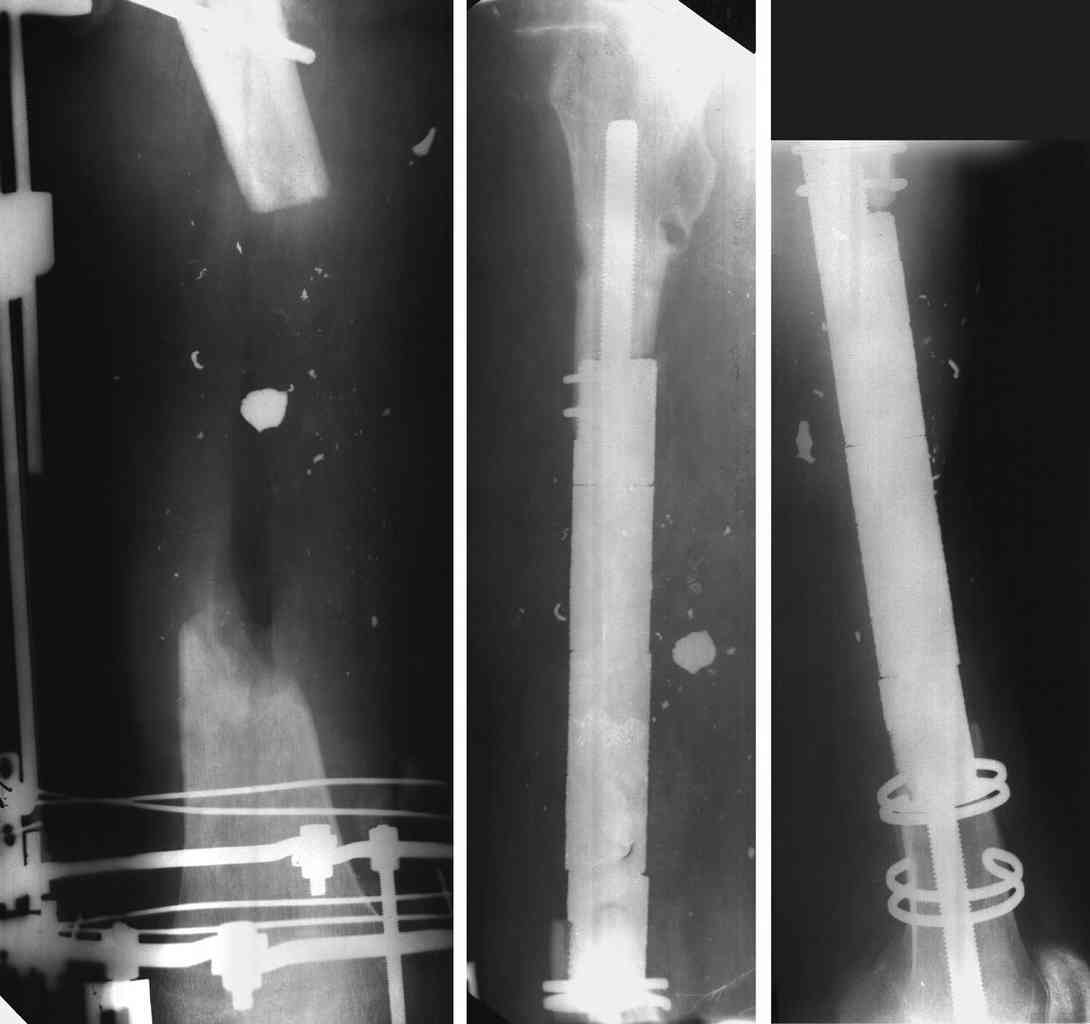

There are 3 main options:

1 Ilizarov bone transport

2 Vascular fibular graft+plating

3 Diaphyseal endoprosthesis - see photo (dangerous in soft tissue loss and infection)